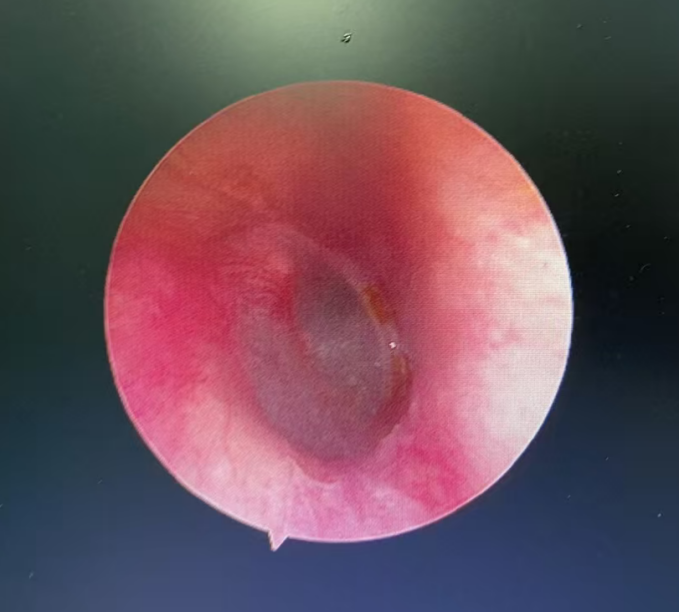

经急诊转诊到耳鼻咽喉头颈外科,医生用电耳镜进行观察,发现一只蟑螂卡在外耳道深处。金先生一直喊疼,并说感觉到耳道内物体的活动。“别怕,我先用石蜡油把虫子杀死,虫子有点深,晚点再通过耳内镜帮你取出来。”医生一边操作一边安抚金先生。

不久后,确认蟑螂已被“处死”,金先生疼痛暂时缓解,大清早又赶紧去做耳内镜,医生最终用镊子从金先生外耳道取出了指甲盖大小的蟑螂,并为他进行耳道消毒。

鼓膜完整

虫子便不会钻进大脑